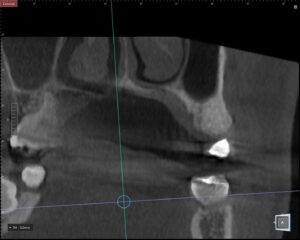

インプラント治療で最も重要なのは「正確な診断」です。歯ぐきの中の骨の厚みや神経・血管の位置は目では見えません。当院では歯科用CTを使用し、骨の状態を三次元で把握します。これにより、安全な埋入位置や角度を事前に計画することが可能になります。

CTデータをもとにデジタルシミュレーションを行い、ガイド手術を実施します。ガイド手術とは、事前に設計した位置に正確にインプラントを埋入するためのマウスピース型装置を使用する方法です。経験や感覚だけに頼るのではなく、データに基づいた治療を行うことで、誤差を最小限に抑えます。